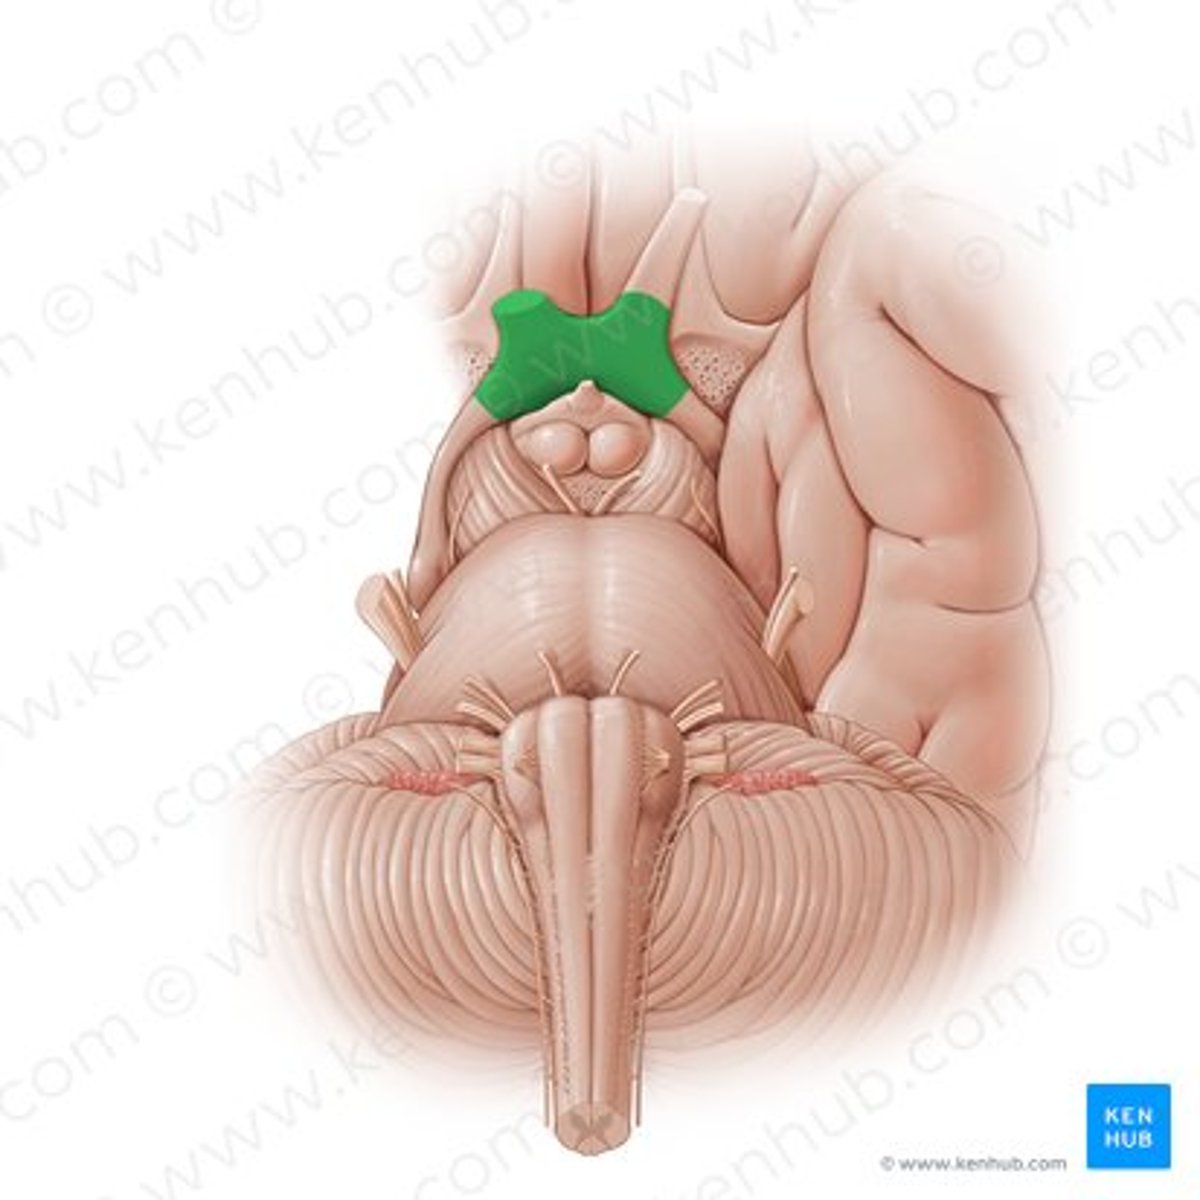

optic chiasm